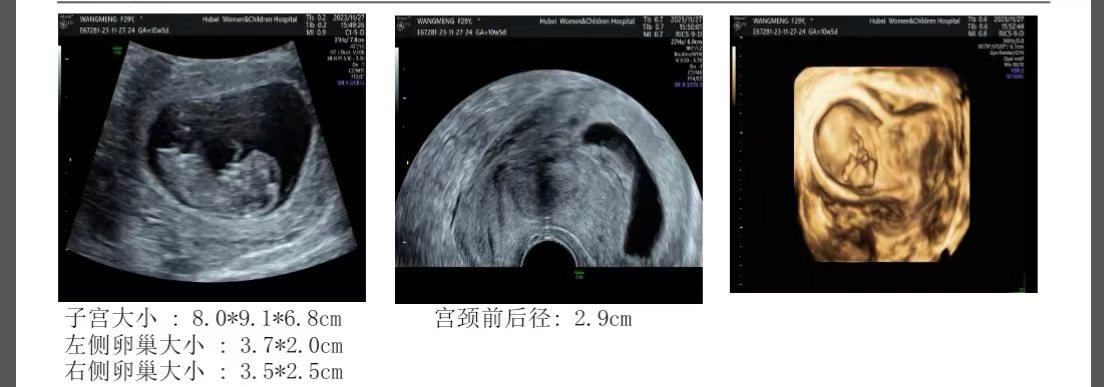

慕名看了我的门诊,显示孕囊距离子宫浆膜层仅4mm,因为她没有孩子,所以只能期待着、祈祷着宝宝能够长到宫腔中间来一点。但是到孕11周还是子宫角部肌层非常薄仅2.8mm,琴非常担心子宫破裂,与丈夫商量好决定放弃这个总是在偏远角落的孩子!

孕10.6周,孕囊右侧缘肌层厚0.28cm